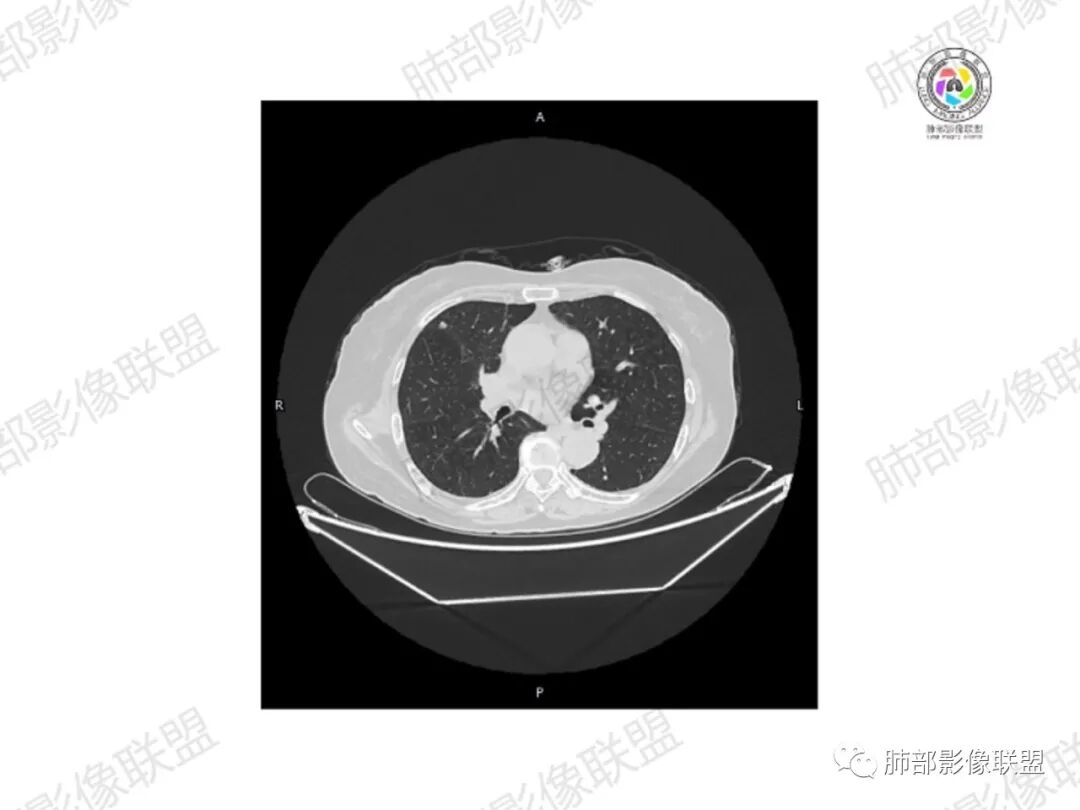

5.双肺多发类圆形结节影,边界清楚,随机分布,其间多见钙化密度影。

6.双肺门及纵隔未见肿大淋巴结。

3.双肺病灶符合转移瘤,伴有中央部分钙化者也以骨肉瘤转移较为多见。

流心明智: 老年女性,直肠癌放化疗术后。胸部CT:双肺多发大小不等实性结节影,边缘光滑,随机分布,胸膜下多,双肺下叶为主,部分结节内有点状高密度,个别胸膜下山丘征。右侧骨盆骨质破坏(溶骨性、成骨性都有),病理性骨折,周围软组织肿块包裹,强化明显,内见多发模糊灶性坏死。考虑恶性,骨肉瘤伴肺转移?肺Ca伴骨转移?直肠Ca伴双肺、骨转移?鉴别骨髓瘤(成骨少),淋巴瘤(其他位置未见肿大淋巴结、肺内部分病灶有钙化趋势)等。